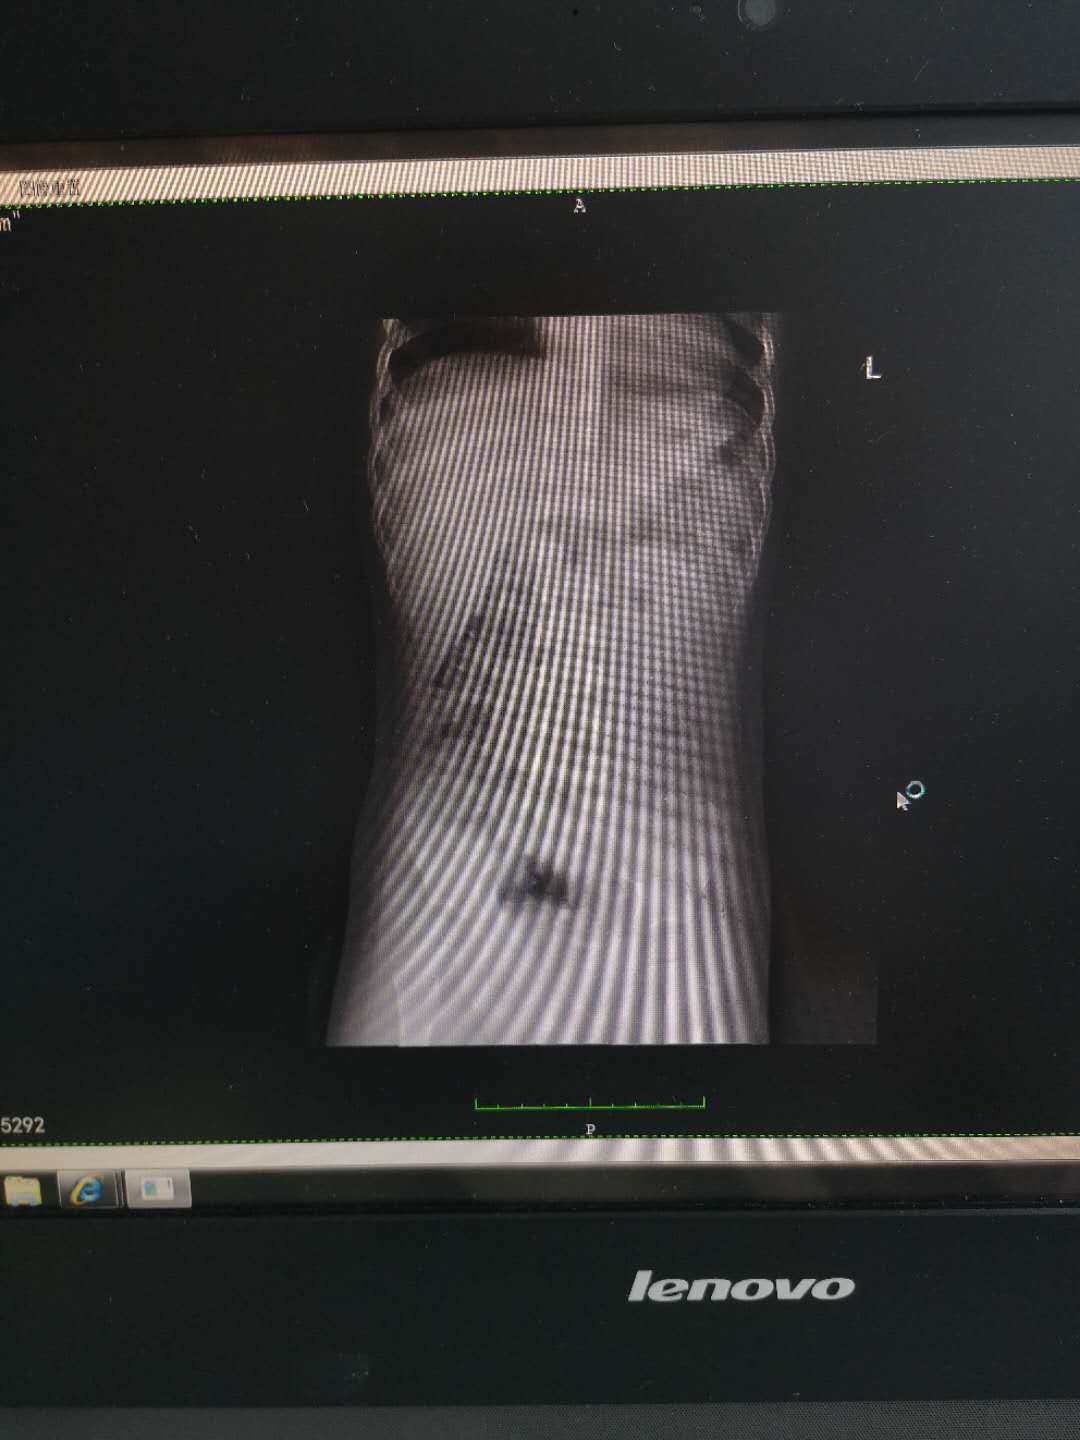

患儿,男,2岁4个月,家住张店洪沟社区,因排尿困难伴疼痛急来医院就诊,经检查确诊为膀胱结石和尿道结石,结石堵塞尿道导致患儿小便时急得满头大汗也排不出来,排出少许还是血尿。医师李鹏在全麻状态小儿膀胱镜下采用钬激光碎石,顺利将结石粉末化后冲洗至体外,手术成功并且患儿无不适。

输尿管中下段结石、膀胱结石、尿道结石患者(结石直径≥0.8cm,结石嵌顿、其周围被息肉包裹或者体外碎石治疗效果不佳者。